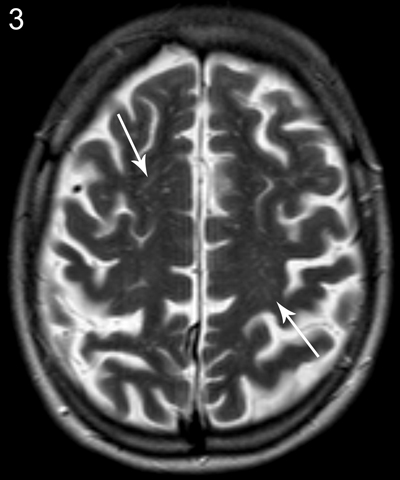

Figure 3

Patient A, axial T2-weighted image shows prominent Virchow-Robin spaces bilateral in the centrum semiovale.